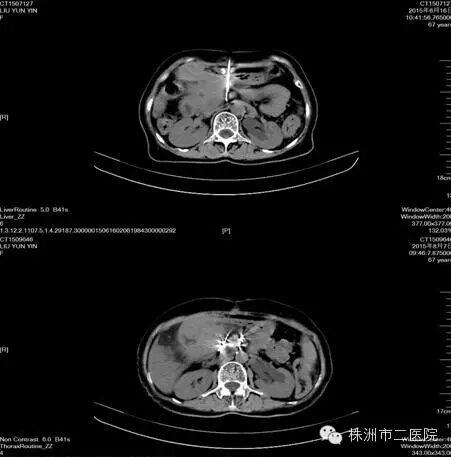

半年前,被癌痛折磨得徹夜難眠、茶飯不思的晚期胰腺癌患者劉娭毑,慕名來(lái)到株洲市腫瘤微創(chuàng)中心----株洲市腫瘤醫(yī)院(株洲市二醫(yī)院)腫瘤一科,她對(duì)腫瘤學(xué)科帶頭人馬恩奇主任說(shuō):我來(lái)貴科的唯一目的就是控制疼痛。原來(lái),劉娭毑因?yàn)榇_診時(shí)病情太晚,當(dāng)時(shí)就無(wú)法手術(shù),腰背部疼痛折磨了她已經(jīng)幾個(gè)月,服用嗎啡類止痛藥不僅未緩解疼痛,而且毒副反應(yīng)大。她聽(tīng)熟人介紹說(shuō)我院腫瘤一科是我市的“癌痛規(guī)范化治療示范病房”(無(wú)痛病房),于是抱著試試看的態(tài)度來(lái)到了我科。馬主任認(rèn)真查閱病歷并組織全科討論后認(rèn)為:患者疼痛是由于胰腺腫塊壓迫腹腔神經(jīng)叢而導(dǎo)致的頑固性、難治性疼痛,最后決定采用局部精準(zhǔn)靶向治療---CT導(dǎo)引下放射性粒子植入術(shù)(通俗來(lái)說(shuō)就是腫瘤近距離定向“爆破”)。經(jīng)過(guò)術(shù)前的充分準(zhǔn)備,歷時(shí)一個(gè)多小時(shí),為患者成功植入放射性粒子碘125。一周后患者疼痛明顯緩解,半月后撤掉止痛藥物。前幾天患者神采奕奕地來(lái)我科復(fù)診,復(fù)查CT顯示胰腺腫塊明顯縮小。